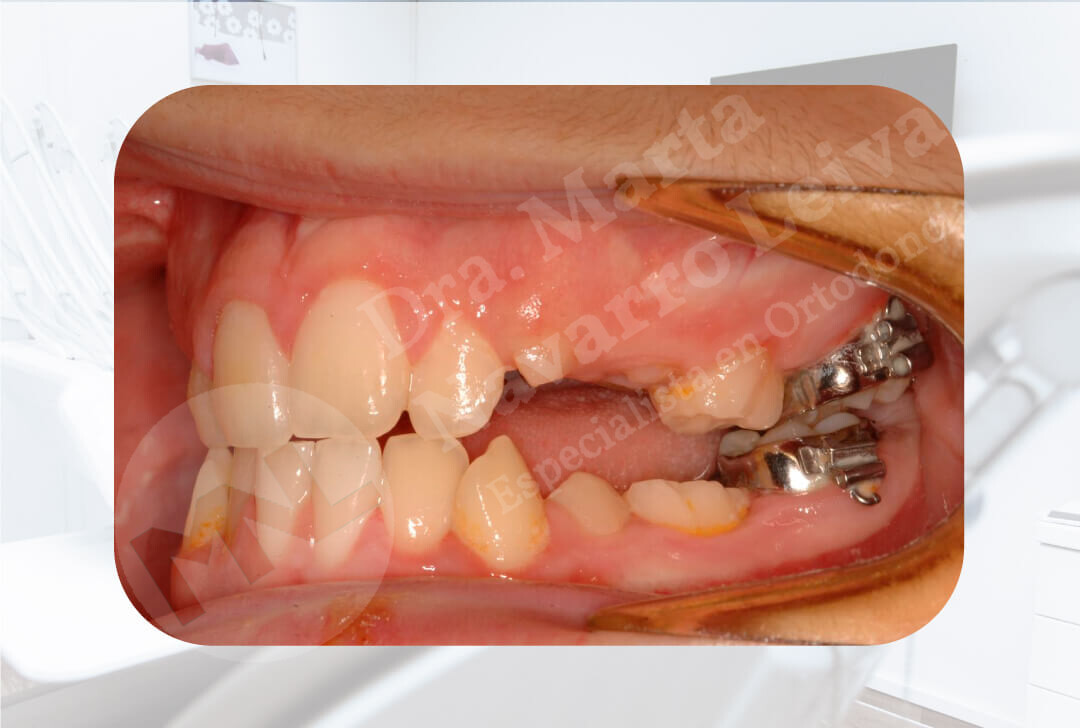

Falta de espacio para la buena colocación y alineación de los dientes.

Deslice libremente el separador en cada uno de los casos para ver las diferencias entre maloclusión y resultado de ortodoncia.

Antes

Antes